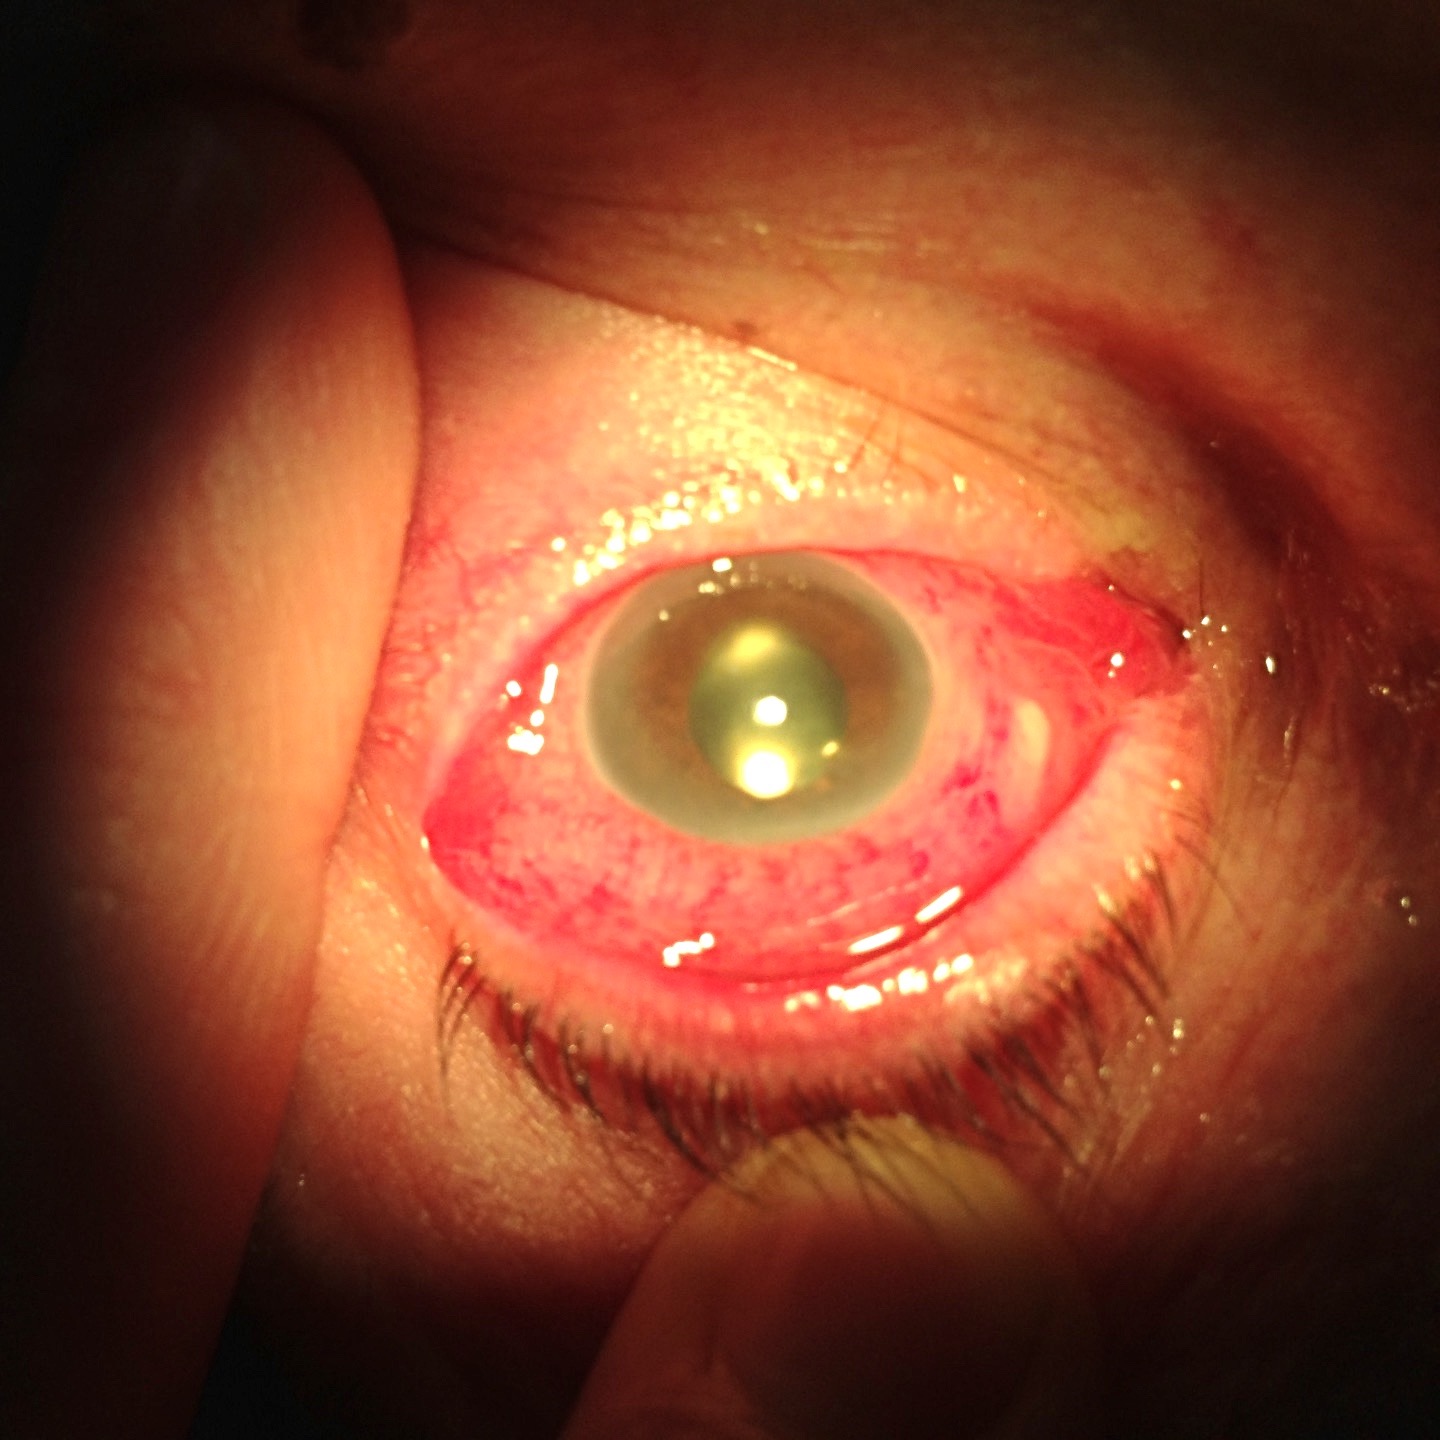

- chirurgie de la cataracte

- urgences ophtalmologiques (conjonctivites, abcès de cornée, traumatismes oculaires...),

Chirurgie de la cataracte, de la rétine et vitréo-rétinienne:

trou maculaire, membrane épi-rétinienne, décollement de rétine...

Urgences ophtalmologiques : conjonctivite, abcès de cornée, traumatisme oculaire...